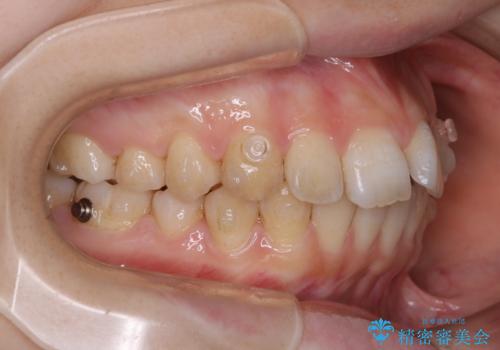

前歯の重なりは奥歯のズレが原因:まとめてインビザラインで治す

- インビザラインFULL

- 前歯の重なりが気になるとご相談にいらした方です。前歯のがたつきは奥歯の噛み合わせのズレが原因となっていたため、インビザラインFULLにて奥歯からしっかり治療していきました。

見た目だけでなく奥歯を移動させて噛み合わせの改善までが行えるのはインビザラインであるからこそです。奥歯の噛み合わせからしっかり機能させることで、長期間にわたって綺麗な歯並びを保ちやすくなります。